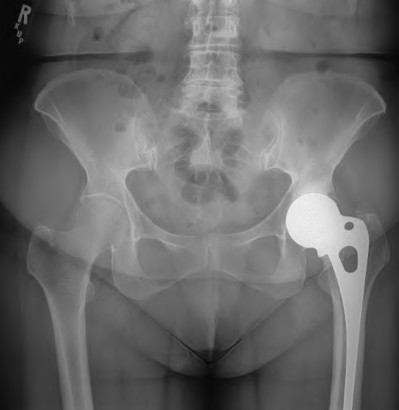

ORTHOPEDIC MCQS ONLINE RECON OB 20 1C 2020 A 72-year-old female presents with progressive left thigh and knee…